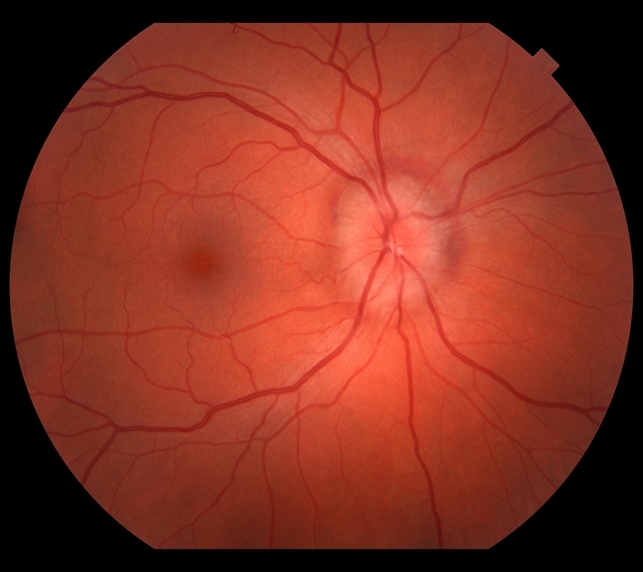

Медицинские исследования: эластическая псевдоксантома